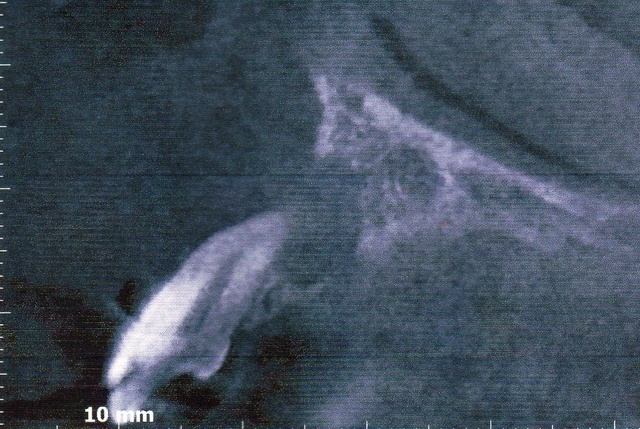

上顎 右上側切歯 の歯ぐきが腫れていた患者さんです。

パノラマ写真(2D)では、根尖部に黒い影がみえます。

CT画像(3D)で確認すると、根尖部の骨も溶けているのがわかります。